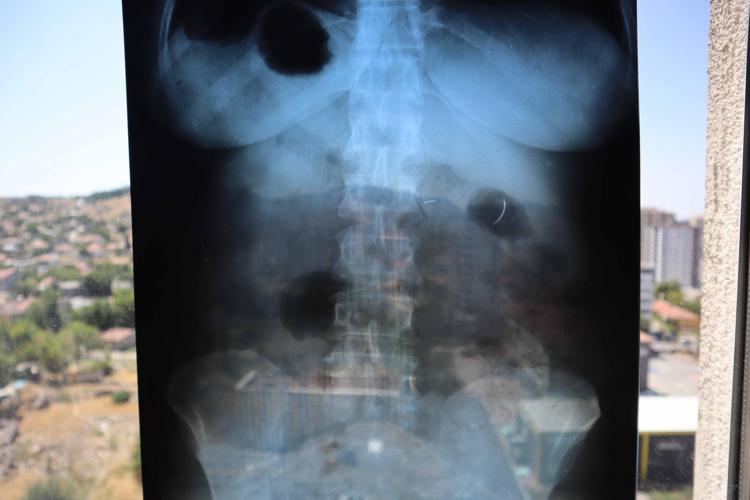

Kentte yaşayan 2 çocuk annesi Ayhan Tanyıldız, 2003 yılında karaciğerindeki kist nedeniyle ameliyat oldu. Ameliyat olduktan 6 yıl sonra böbrek rahatsızlığı nedeniyle hastaneye giden Tanyıldız’ın çekilen röntgeninde iğne görüldü. Tanyıldız’ın kist ameliyatı sırasında karnında ameliyat iğnesi unutulduğu ortaya çıktı. Kendisini özel hastanede ameliyat eden Genel Cerrahi Doktoru İ.D.’ye dava açan Tanyıldız, ağrılarının nedeninin karnında unutulan ameliyat iğnesi olduğunu öğrendi.

19 yıl sonra mahkemesi de sonuçlanan Tanyıldız, bir miktar tazminat almaya hak kazandı. 22 yıldır ameliyat iğnesiyle yaşayan Tanyıldız, “2003 yılında ameliyatım yapıldı. Karaciğerimdeki kistten dolayı ameliyat oldum. Karaciğerimde kist oluşmuş. Kisti alırken ameliyat iğnesini unutmuşlar. 6 yıl sonra fark ettim. İlk öğrendiğimde başka doktora gittim, böbreklerimden rahatsızlanmıştım. Doktor film çekince ‘sen MR’a girme, ciğerinde iğne var’ dedi. O zaman fark ettim. Fiziksel olarak hala ağrısını, yıllardır çekiyorum” diye konuştu.